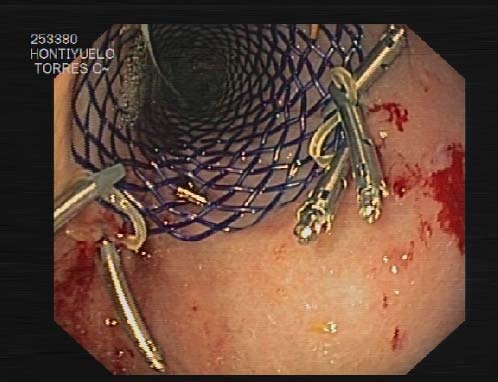

few cases in the literature that use a stent to The first option we chose was the endoscopic dilation, butafter 3 attempts, it was not effective and the patient continued with intolerance to food. The second option was to place an undercover metallic stent by interventional radiologists, under general anesthetic. Initially it was effective but after 3 days, the stent migrated cranially. Finally, a 135mm length biodegradable SX-ELLA stent esophageal HV BIOMED® (ELLACS, Hradec Kralove, Czech Republic) was placed from the second portion of the duodenum to the prestenotic side of the gastric tube. This stent was endoscopically fixed with clips at its proximal portion to prevent its proximal migration (Figures 4 and 5). After two days of having placed the biodegradable stent, the oral contrast study was done and it showed no stenosis in the gastric tube (Figure 6). The patient was discharged on the third day after placing the stent eating soft food. After 5 months of stenting, the patient is completely asymptomatic.

We report a case of a woman with squamous cell carcinoma in the middle third of the esophagus where a three-field esophagectomy was carried out. The patient presented food intolerance in the immediate postoperative period due to the rotation of the gastric tube. First of all, we tried to dilate the functional stenosis but it did not work because the endoscope couldn´t keep the twisted tube open. We also placed a covered metallic stent but the stent had cranially migrated by the third day. Finally, we decided to place a biodegradable stent from the second duodenal portion to the prestenotic area of the plasty by interventional radiologist. Furthermore, the endoscopist fixed with clips the most proximal side of the stent to the mucosa of the gastric tube. Two days later the oral contrast study showed that the stent was correctly in its place and had not migrated. After that, the patient started with the oral intake. Five months have passed since the biodegradable stent was placed and the patient has been asymptomatic with good oral tolerance both for liquids and solids. The purpose of placing a biodegradable stent was for twofold: first, because the long-term degradation of the stent would keep the functional stenosis open and second, because in this way the stent does not require removal.